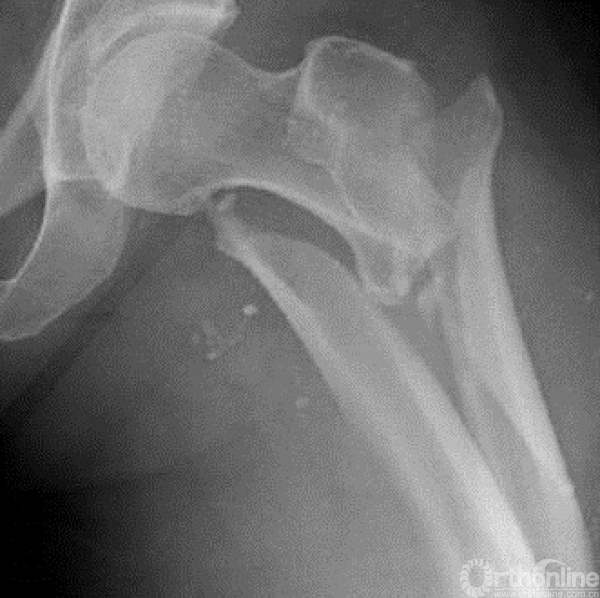

进针点不良会导致复位出现内外翻。

好的进针点。

不好的进针点。

进针点选取的时候,一定注意腿的旋转。以小粗隆为参考,小粗隆稍微重叠1/3时一般为正位。